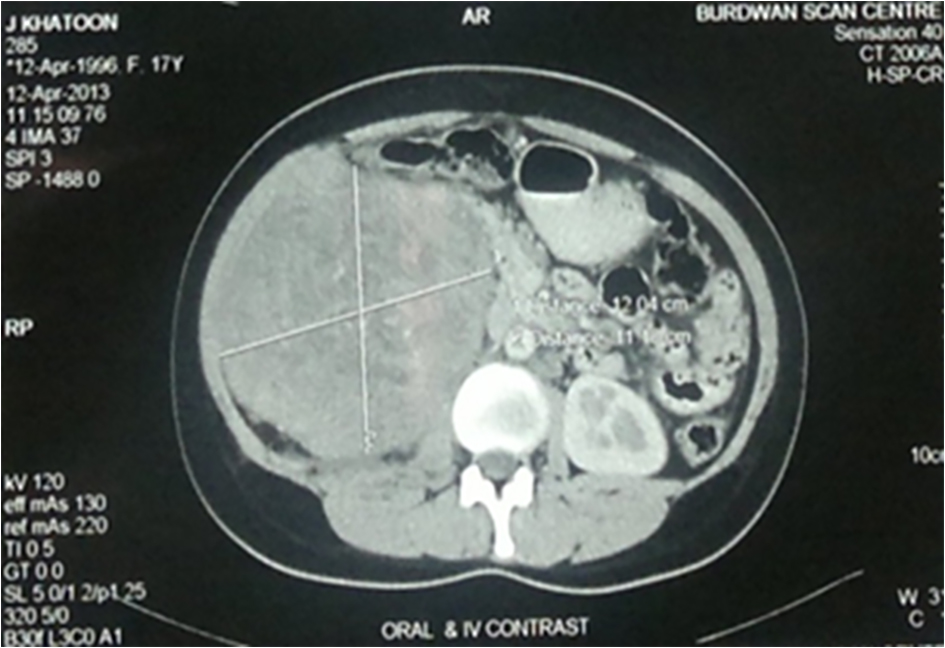

A 17-year-old girl presented to us with right flank pain of 2 weeks duration. Her medical history was unremarkable. On physical examination, there was a 15 × 10 cm hard mass occupying the right hypochondriac, lumbar, epigastric and right iliac fossa region, moving with respiration, bimanually palpable and ballotable. No free fluid was noted in the abdomen on examination (Fig. 1). All the routine blood investigations including serum creatinine were normal. Urine analysis was normal. An ultrasound of the abdomen showed a large heterogeneous solid tumor (192 × 108 mm) arising from the right kidney. Few hilar lymph nodes were noted. There was no evidence of liver metastasis/ascitis. A contrast-enhanced computerized tomogram revealed heterogeneously enhancing 12 × 11 cm mass occupying the inter-polar region and lower pole of right kidney, posteriorly infiltrating the psoas fascia with multiple hilar lymph nodes (Fig. 2). There was no metastasis to lungs or liver. A USG-guided core biopsy was done which was suggestive of small round cell neoplasm with IHC positive for vimentin and CD99 and negative for cytokeratin, WT1, chromogranin and myogenin suggestive of EWS. Patient was planned for right radical nephrectomy. Intraoperatively, a right renal mass measuring 20 × 13 cm was noted arising from the lower pole and infiltrating into the right colon and psoas fascia. Right radical nephrectomy with right hemicolectomy was performed (Fig. 3). Histopathology revealed small round to oval nuclei with finely dispersed chromatin and scanty ill-defined cytoplasm with rosette formations. IHC was same as core biopsy (Fig. 4). Postoperative period was uneventful. Postoperatively, she has received adjuvant etoposide-based chemotherapy. Presently she is doing well at the time of this writing.

![]() Click for large image | Figure 2. Computed tomographic image of the right kidney. |